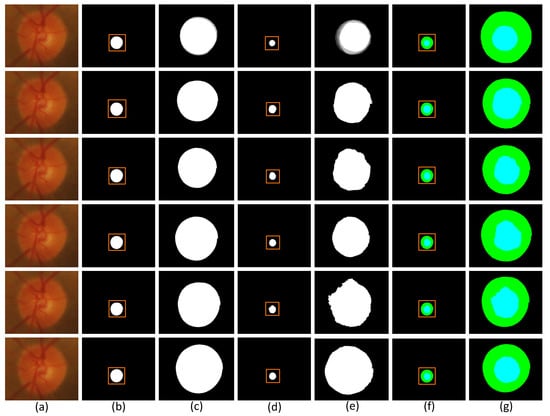

Figure 8.

Comparison of segmentation images of each model in the Drishti-GS1 dataset. (a) Original image (b) Segmentation image of disc (c) Partial segmentation image of disc (d) Segmentation image of cup (e) Partial segmentation image of cup (f) Segmentation image of optic (g) Partial segmentation image of optic.

Each row of Figure 8 shows the visualization segmentation results for the optic disc and optic cup corresponding to each model on the Drishti-GS1 dataset. Since the segmented images were too small to be easily observed, we zoomed in on the visualization results for the optic discs and optic cups.The first row of the figure shows the original image of the optic disc cup along with the corresponding ground truth and the corresponding magnified image. The second row is the segmentation visualization of the baseline network model experiment. The third row is the segmentation visualization of the network model, adding the SMCF module. The fourth row is the segmentation visualization of the network model joining the SRL layer. The fifth row is the segmentation visualization of the network model, adding the MBCM module. The sixth row is the segmentation visualization of MSMB-Net. In addition, we can determine the difference between the different network models by looking at the magnified edges in the optic disc view cup visualization. Comparing the partially enlarged images of different module combinations, we can see the effectiveness of MSMB-Net segmentation. The optic disc cup area is also enlarged and displayed. Through the enlarged image, it can be seen that the contour of the MSMB-Net model is more consistent with the real label during the segmentation of the optic disc. Compared with other combined models, the segmentation contour of the optic cup of the MSMB-Net model is more accurate and perfect than other models.